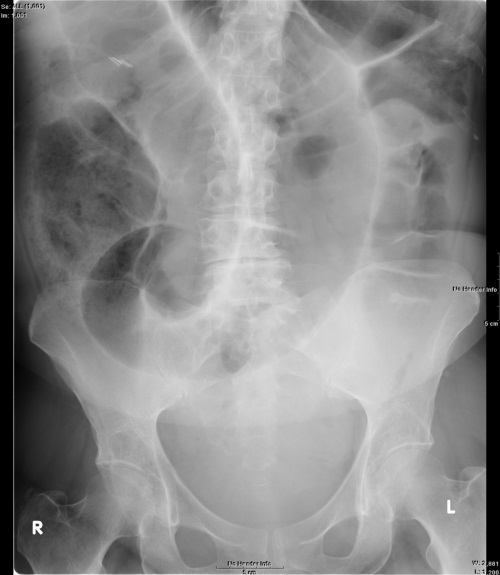

What does this Abdominal polain radiograph show?

Sigmoid volvulus.

Clear “coffee bean sign” and large-bowled obstruction.